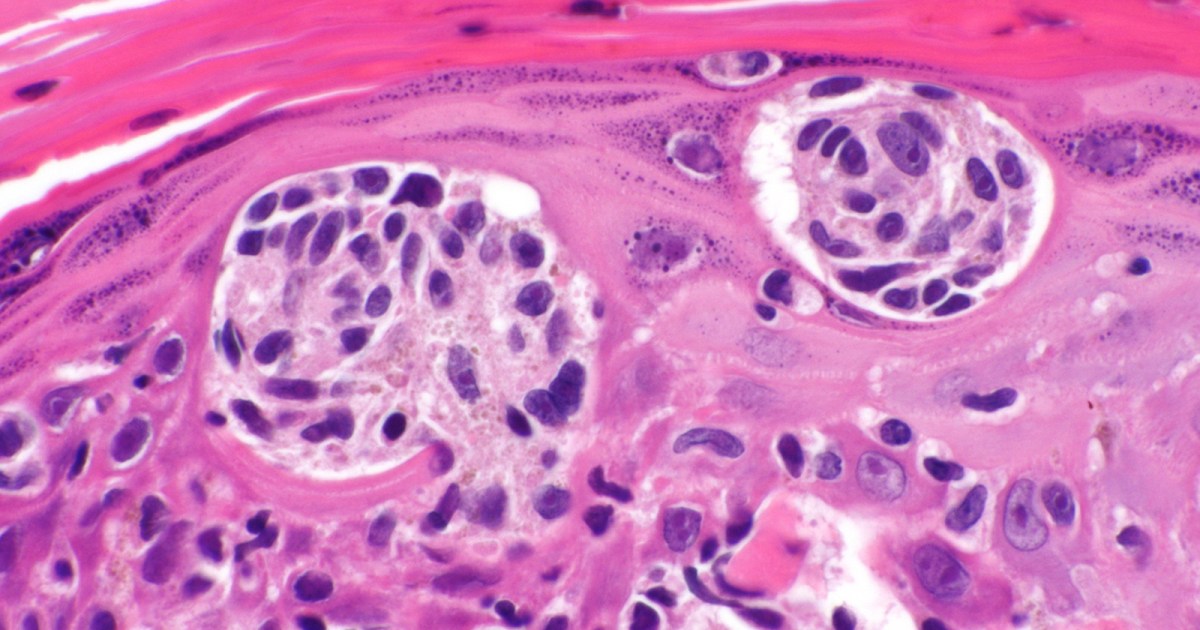

The personalized shot gives a standard melanoma treatment a huge boost.

Moderna's new mRNA cancer vaccine significantly reduced skin cancer patients' risk of recurrence or death compared to a standard treatment alone, according to the newly announced topline results of a phase 2 trial.